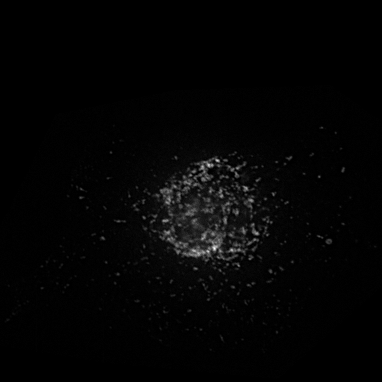

Microscopy techniques are employed to capture subcellular localization images of proteins in a cell, which were previously analyzed using traditional wet methods. However, advances in microscopy techniques have brought an avalanche of medical images in a considerable amount; hence, manual analysis and processing of these medical images become nearly impossible for biologists. Moreover, a subjective inspection of images may lead to errors in decision-making process shao2017deep ; tahir2011protein ; kreft2004automated . It is highly likely that the images generated for proteins of the same class may look visually different (see Figure 1). Similarly, proteins belonging to two different classes may look alike. Such a situation leads to the poor performance of classification systems. These problems are resolved by applying different hand-crafted feature extraction strategies to capture multiple views from the same image tahir2016protein . Hence, this is a cumbersome job and may fail to discriminate with high accuracy.

Prediction confidence: We compare the prediction confidence of traditional classifiers trained on Yeast and HeLa datasets against our PLCNN on four images as shown in Figure 11. Each image has the prediction probabilities for each algorithm underneath. The red color shows when the prediction is incorrect, whereas the green is for the correct outcome. It can be observed that our method predicts the correct labels with high confidence, while the probability is very low when the prediction is incorrect. The image in the first column in Figure 11 is very challenging due to minimum texture and almost no structure. All the methods failed to identify the type of protein in the mentioned image correctly. However, the competing methods prediction scores are much higher than ours. Similarly, our algorithm confidence is always high when the prediction is correct and low when it is incorrect. This shows the learning capability of our network.

![]() |

|

| AlexNet | 0.32 | 0.57 | 0.79 | 0.82 |

|---|---|---|---|---|

| ResNet | 0.69 | 0.68 | 0.49 | 1 |

| DenseNet | 0.60 | 0.79 | 0.75 | 0.90 |

| PLCNN | 0.26 | 0.88 | 1 | 1 |